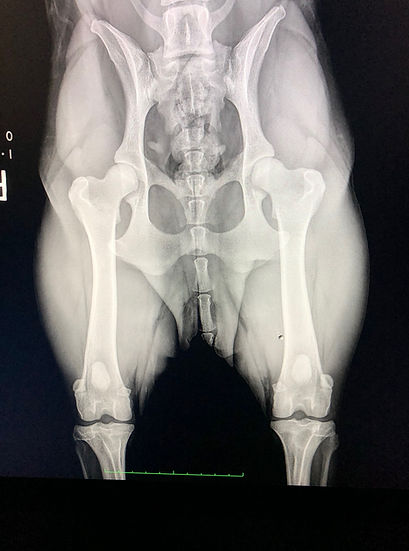

CEA/CL Clear and normal by parentage BCG normal, Full Dentition, OFA HIPS: Good 20"+ at withers